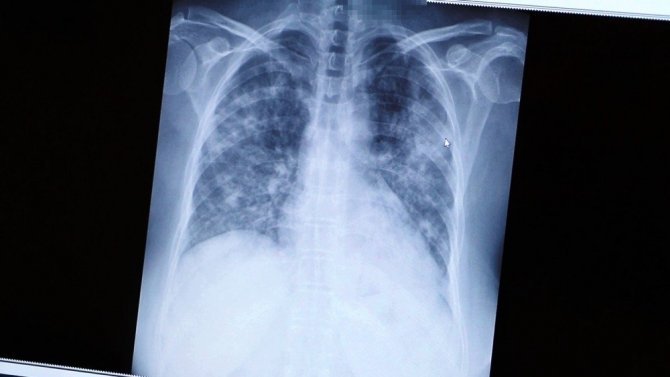

Önce sağlık çalışanlarının aşılanacağını belirten Prof. Dr. Özkaya, "Doğrusunu söylemek gerekirse bu incelediğimiz tomografi, ölümden kıl payı kurtulan bir doktor arkadaşımın tomografisi. Gördüğünüz gibi kendisi canla başla Kovid-19 hastalarını tedavi ederken hastalığa yakalandı. Günlerce hayati tehlike yaşadı. Önce sağlık çalışanlarını aşılayacağız çünkü sağlıkçılar ne kadar güçlü olursa toplumun da o kadar güçlü olacağını düşünüyoruz. Bu görüntüsünü gördüğünüz film de 40'lı yaşlarda bir hastamızın akciğer filmi. Gördüğünüz gibi yaygın bir akciğer tutulumu var. Biz normalde 65 yaş üstünü sokağa çıkmayı yasaklıyoruz ama gördüğünüz gibi 40'lı yaşlarda da çok ciddi akciğer tutulumuyla gelen hastalar oluyor. Bu da bugün kontrole gelen akciğeri pırıl pırıl olan bir hastamız. Herkes bu kadar şanslı olmuyor. Bildiğiniz gibi 65 yaş üstü vatandaşlarımızı bu salgında çok fazla kaybettik. Onlar şu an hala evde hapisler. Toplumda ne kadar çok kişi aşılanırsa bu esaretten kurtulacağımızı düşünüyoruz" ifadelerini kullandı.